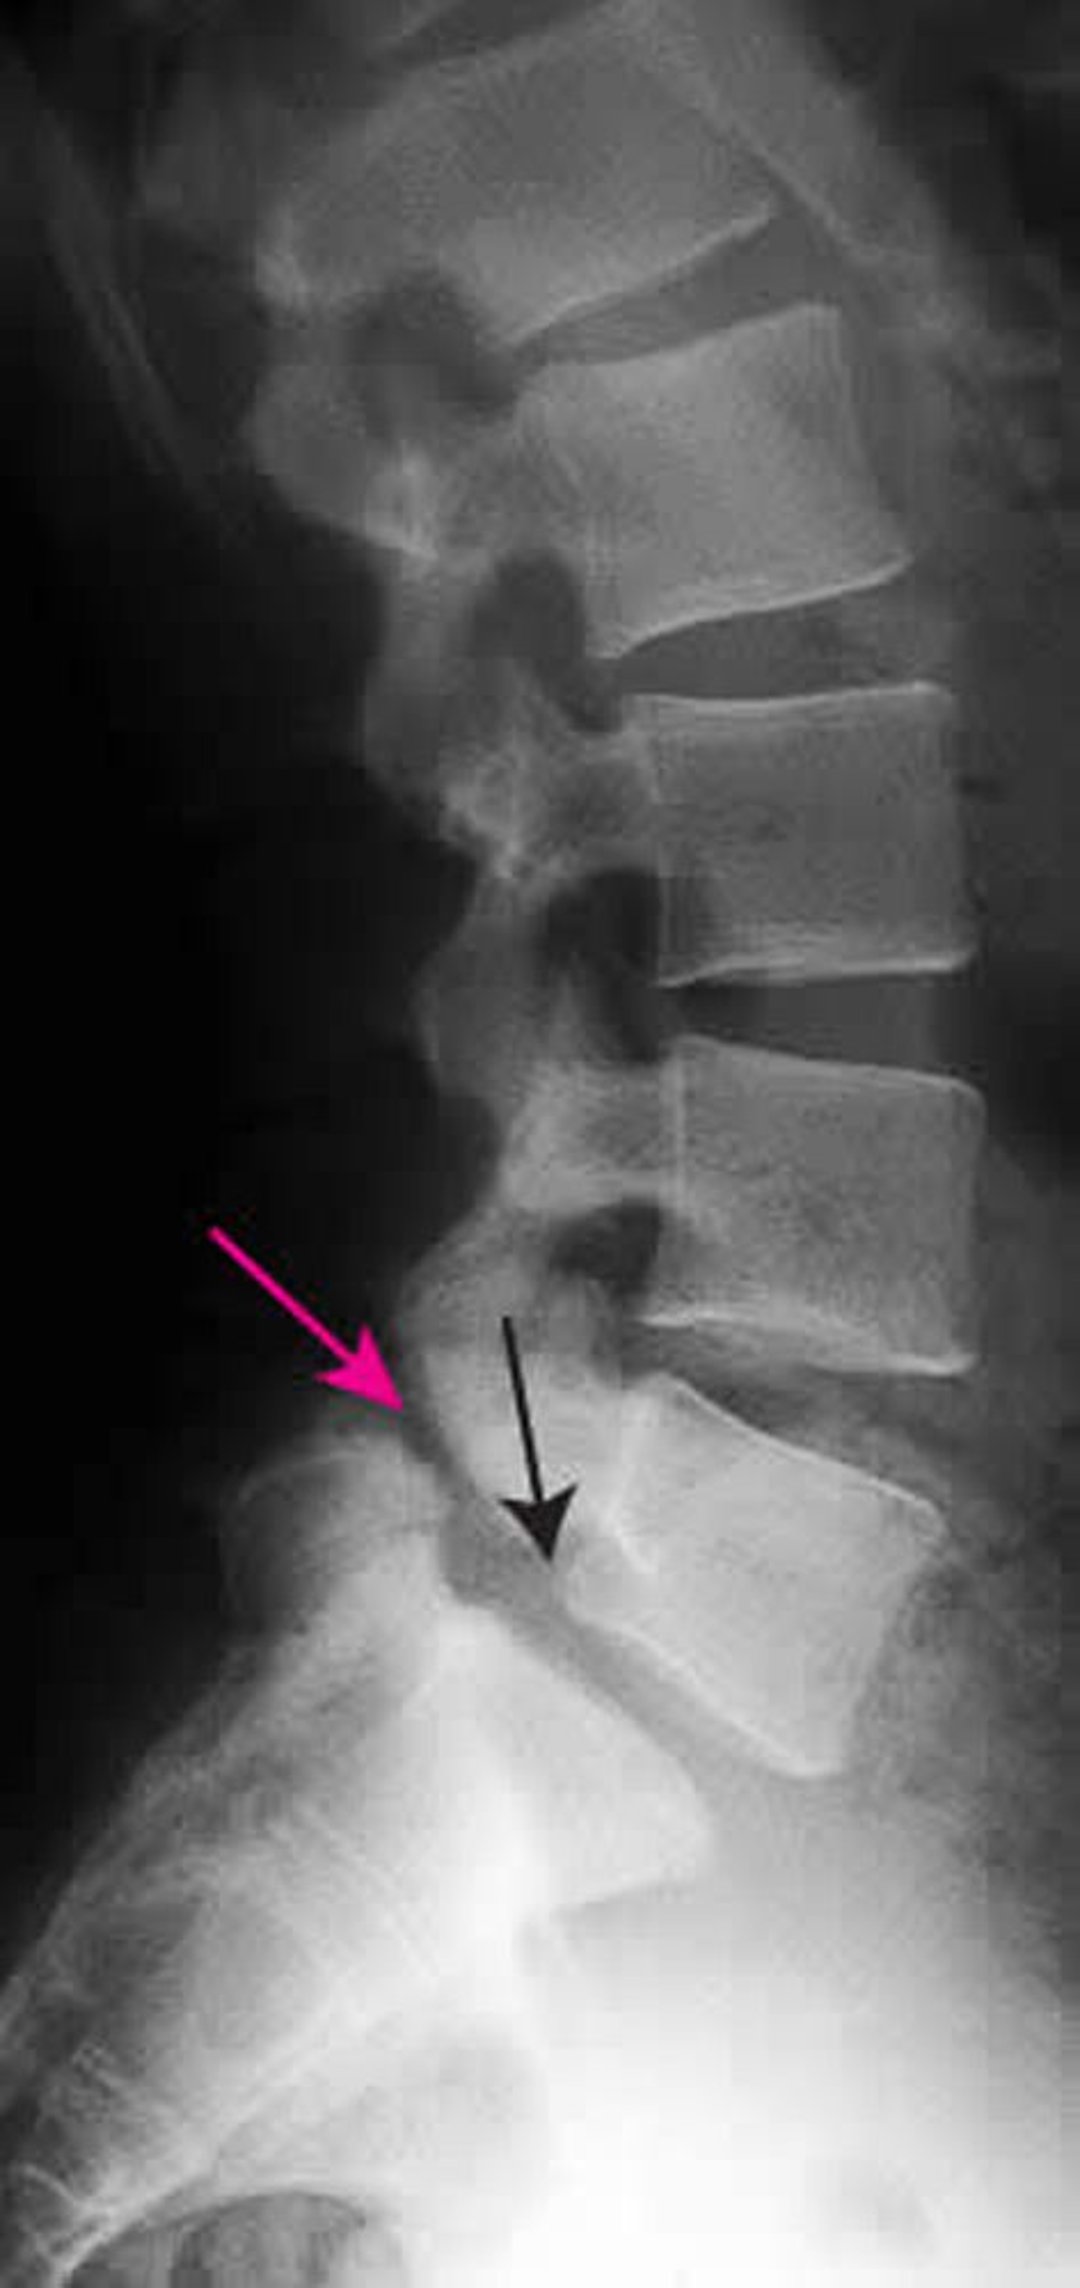

This radiograph shows grade 1 spondylolisthesis of L5 on S1. The black arrow shows the posterior border of L5, which subluxes anterior to S1. The red arrow points to the spondylolysis (defect in the pars interarticularis).